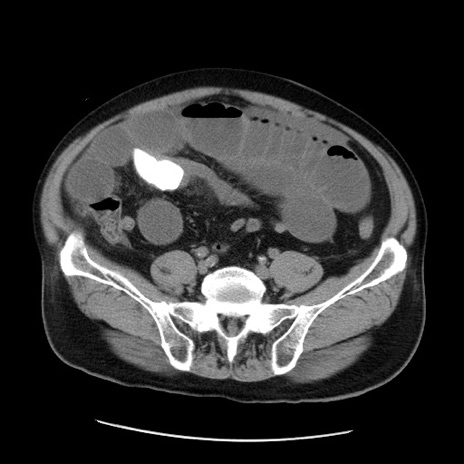

症例20(横断像)

【症例】 60歳代男性

【主訴】 腹部膨満、嘔吐

【現病歴】5日前頃より倦怠感を認め食事量減少し4日前の朝嘔吐、食事摂取困難となった。 3日前近医受診し点滴施行され整腸剤などを処方された。 当日他院を受診し、腹部膨満著明、炎症反応の上昇(CRP10.8、WBC11200)あり、紹介受診となる。

【身体所見】 意識JCS1 受け答えがはっきりしないBP 111/57mHg、 P 67bpm、、BT35.2°C、SpO2 97%(RA)、 腹部:膨隆、打診で鼓音あり、全体的に圧痛有り、腸蠕動音(-)、反跳痛ははっきりせず。

【データ】WBC 11400、CRP 14.20